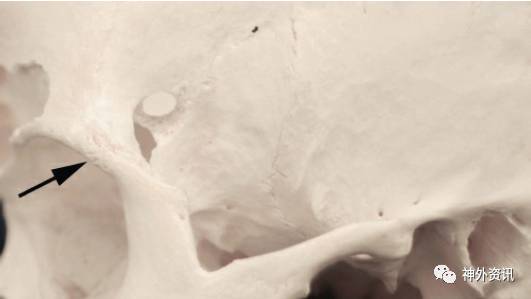

图5:改良眶颧入路移除的骨质包括眶缘、眶顶前部及颧骨额突的一部分。骨质切割范围可延伸至眶下裂,但已很少应用。额颧缝(蓝箭)大约为眶顶水平(感谢Rhoton教授对图片的授权)。

图6:与眶颧入路相关的前外侧颅底的骨性解剖(左上图)。注意从眶内侧面观察到的关键孔与额颧缝的关系(上右图和下左图)。翼点入路中的“关键孔”则位于眶颧入路中的McCarty关键孔的上方,前者仅需暴露额叶硬膜,而后者需同时暴露眶骨膜和额叶硬膜(感谢Rhoton教授对图片的授权)。

图7:关键孔周围的骨缝解剖(左上图)。本人研究发现,为同时显露眶骨膜以及被眶顶隔开的额叶硬膜,最佳的关键孔定位为A1点(右上图)(此处与所引原文观点不同;原文中Rhoton等作者认为最佳定位点为B1;译者注)。注意眶顶与垂直虚线之间呈一夹角(左下图)。眶顶的厚度和倾斜角度存在变异。需熟悉其典型的倾斜角度,以便在术中保证关键孔能同时暴露额叶硬膜和眶骨膜(感谢Rhoton教授对图片的授权)。